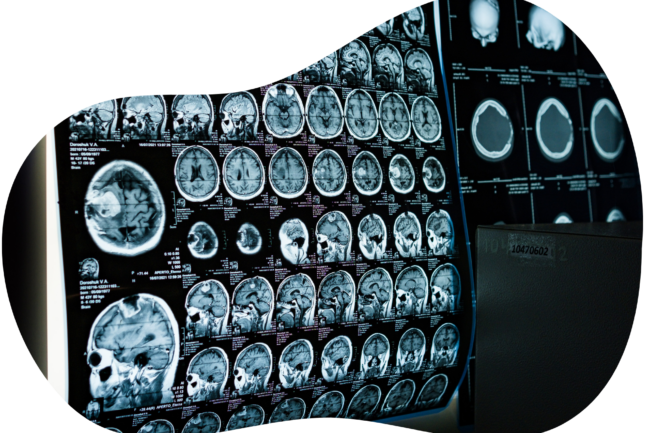

MRI studies show weaker connections between key brain networks during nicotine withdrawal,

indicating a measurable loss in cognitive ability.